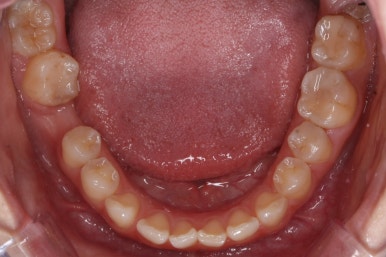

치료 과정을 순차적으로 보겠습니다.

임플란트를 식립하기 위한 공간이 서서히 확보가 되어 가는 것이 보입니다. 어금니만한 사이즈로 공간이 확보가 되면 식립이 이뤄지죠.

불과 4개월만에 장리가 충분히 확보된 모습입니다.